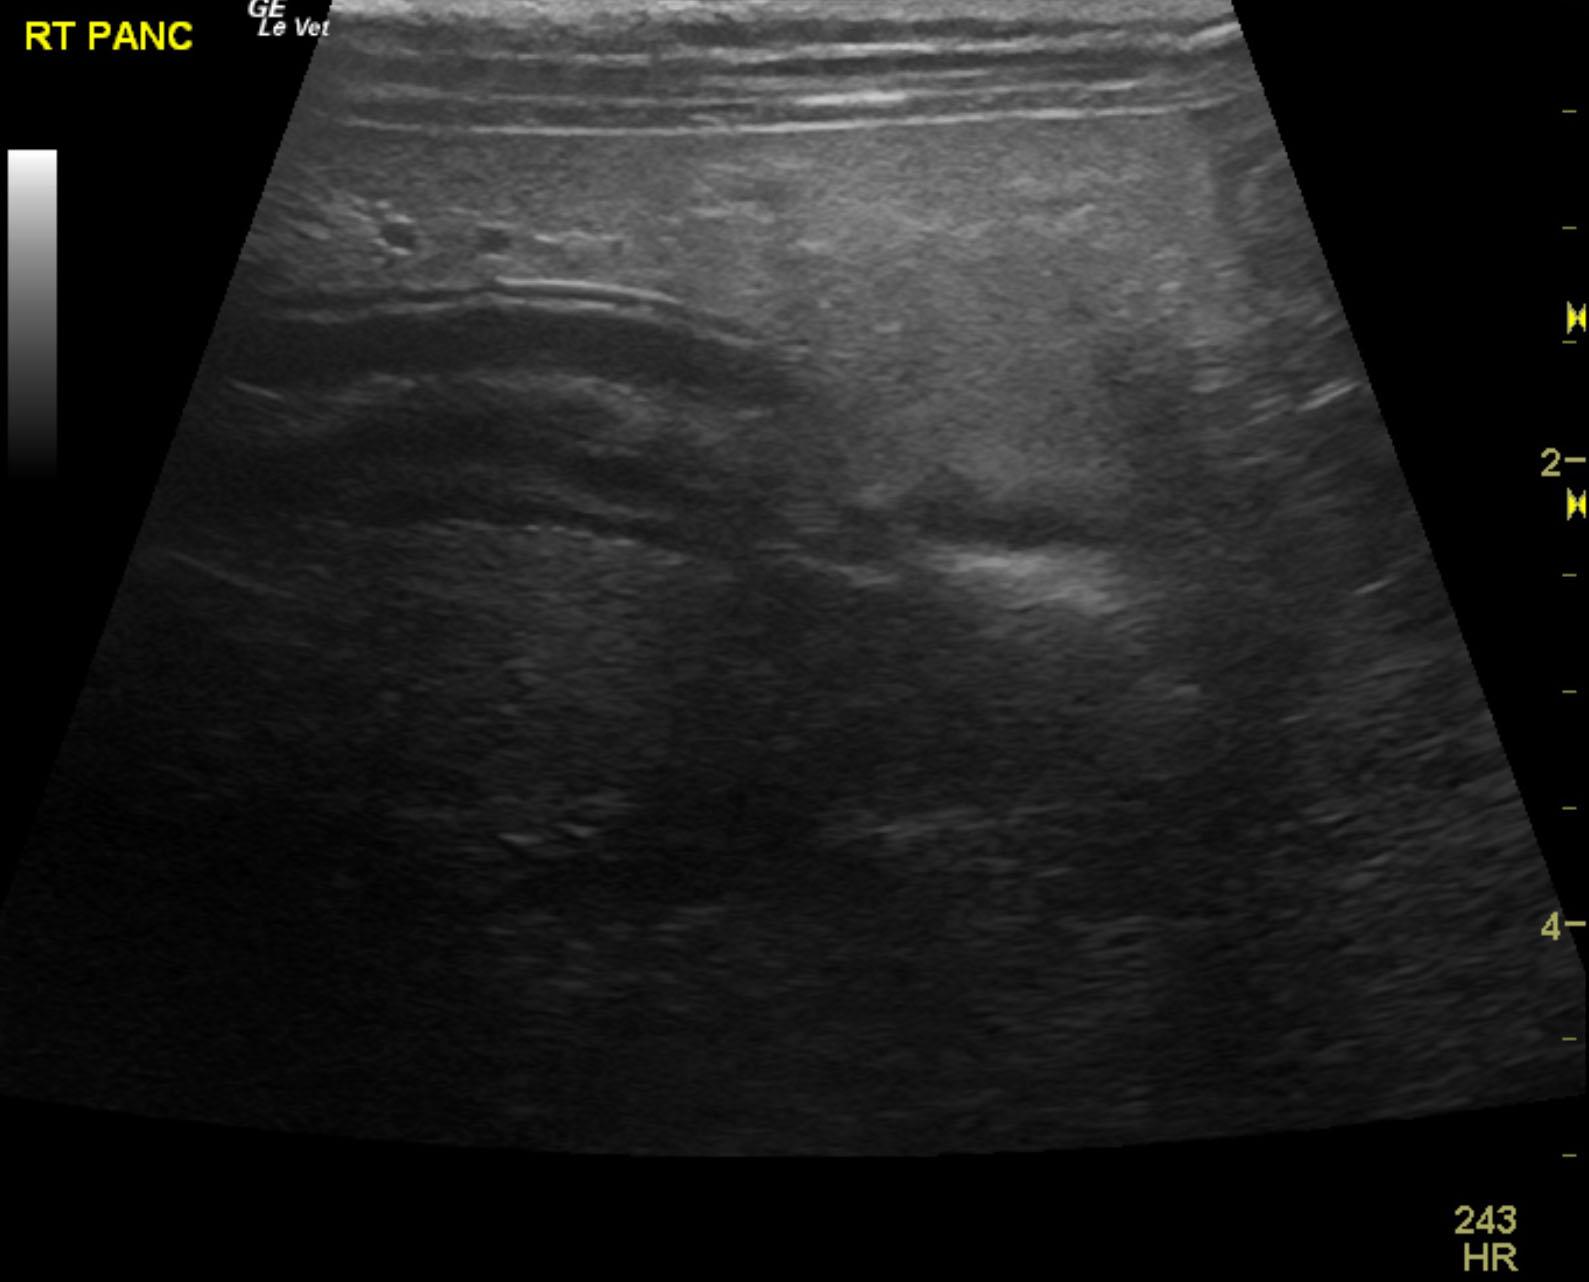

The patient is a 13 year old spayed female Dachshund dog which was presented for four days of anorexia and vomiting. She was given Cerenia, which helped, but still had ileus. Dog has vomited carpet material in past. Spec cPL was normal. Radiographs revealed dilated intestine, which appeared to be colon and cecum.